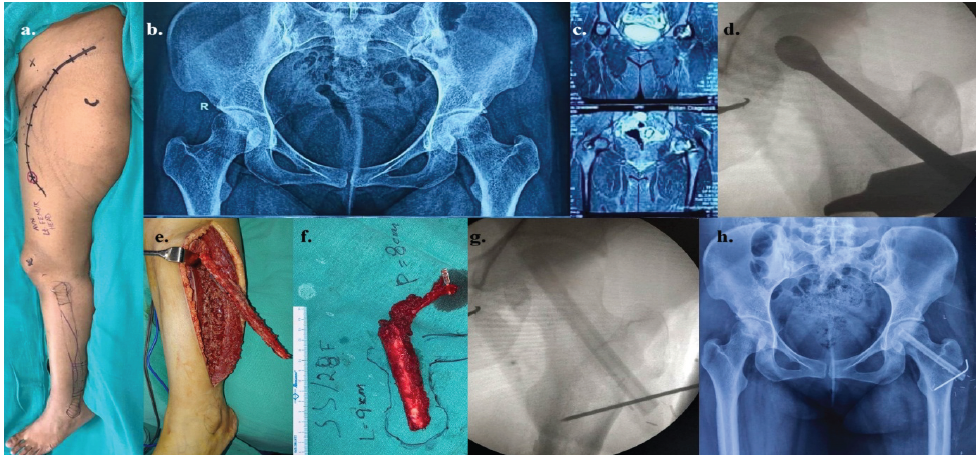

Figure 3: The details of lt. osteonecrosis of femoral head in a 27-year-old female as a sequela to high dose of corticosteroid during COVID-19 – (a) pre-operative picture of the lt. hip and lower extremity with the marked incisions; (b) pre-operative skiagram pelvis anteroposterior (AP) view; (c) pre-operative computed tomography-scan of pelvis; (d) intraoperative image intensifier view of the reamer inside the lt. Femoral head; (e) intraoperative fibula harvest; (f) planning and orientation of fibula after flap detachment; (g) intraoperative picture of image intensifier after introduction of fibula and fixation with K-wire; and (h) post-operative follow-up skiagram pelvis AP view after 3 months.

Four of the patients were males and one female. The minimum age of the patients was 12 years and maximum 47 years with a mean age of 24.8 years. Out of the three patients having ONFH, the first one had type B stage 2, second one type C1 stage 3A, and the third one type C2 stage 3B disease. Out of the three ONFH cases, one patient was a sufferer of sickle cell disease and the other two patients were the sequelae of high intake of corticosteroid drugs received during treatment of COVID 19. All three patients with ONFH were treated with core decompression of necrotic bone and replacement with vascularized segments of fibula (Figs. 1, 2, 3).